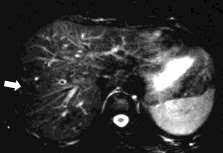

Imaging Of Calcified Hepatic Lesions Spectrum Of Diseases Springerlink